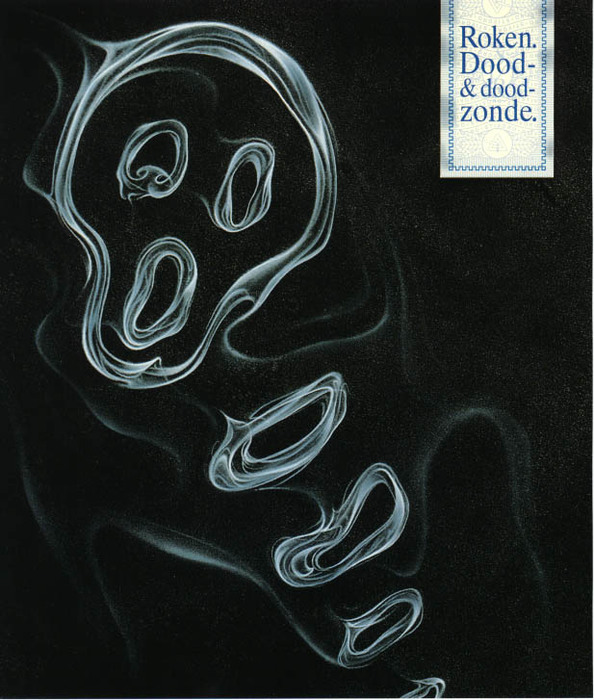

It concerns (harmful) combustion products of tobacco that have lodged in the lungs of smokers. These are stubborn substances that contaminate the inside of the trachea and lungs and stick to it (and cause damage!) for a long time. Even hours after smoking, the smoker’s breath still stinks, demonstrable proof that those harmful products act on the sensitive lung tissue for a long time. Just think of clothing that also smells very long after being in a smoking environment. The lungs of smokers come into contact with the cigarette smoke much more and more directly, and unfortunately we cannot wash our lungs out. The lung structure is very ingeniously put together and the lungs are wonderful, but sensitive organs. It’s a shame that some people want to destroy these organs in such a way.

I would by no means suggest that the smokers still release carcinogenic substances after their cigarette. Most of the carcinogens remained in their lungs and were already absorbed by their bodies. It would go a bit far if we stopped letting smokers in, wouldn’t it? There is no reason for that. Smokers are usually in control of their health problem, literally and figuratively.